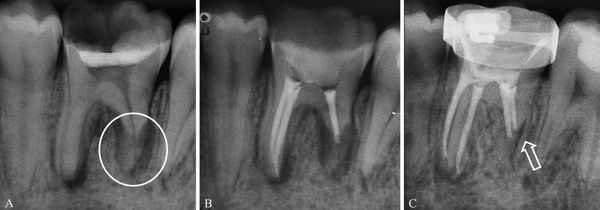

Дополнительные методы обследования: было проведено диагностическое рентгенологическое исследование. При анализе внутриротовой контактной рентгенограммы зуба 1.5 отмечался очаг разряжения костной ткани в области верхушки корня зуба 1.5 (рис. 2). Рис. 2. Внутриротовая контактная рентгенограмма зуба 1.5 до лечения. При проведении электроодонтометрии зуба 1.5 было получено значение более 100 мкА. При проведении термометрии зуб 1.5 не реагировал на холодовой и тепловой раздражители.

В результате проведения основных и дополнительных методов обследования был поставлен диагноз: хронический апикальный периодонтит зуба 1.5 (К04.5). Однако наличие внутренней корневой резорбции было выявлено только в процессе эндодонтического лечения зуба.

Часто резорбцию выявляют случайно при рентгенологическом исследовании по другому поводу [23] . На рентгенограмме внутренняя и внешняя резорбция будут выглядеть по-разному.

Рентгенологические признаки наружной и внутренней резорбции корня зуба

Воспалительная и заместительная резорбция рентгенологически очень похожи. Но при заместительной резорбции из-за образования кости на снимке не видно просветления в области периодонтальной щели.

Рентгеновское обследование зубов (дентальные рентгенограммы) — самым простой, быстрый и доступный метод диагностики. Но в сложных случаях, когда не удаётся поставить диагноз, лучше использовать компьютерную томографию (КТ). Этот метод более информативный [22] [23] [26] .